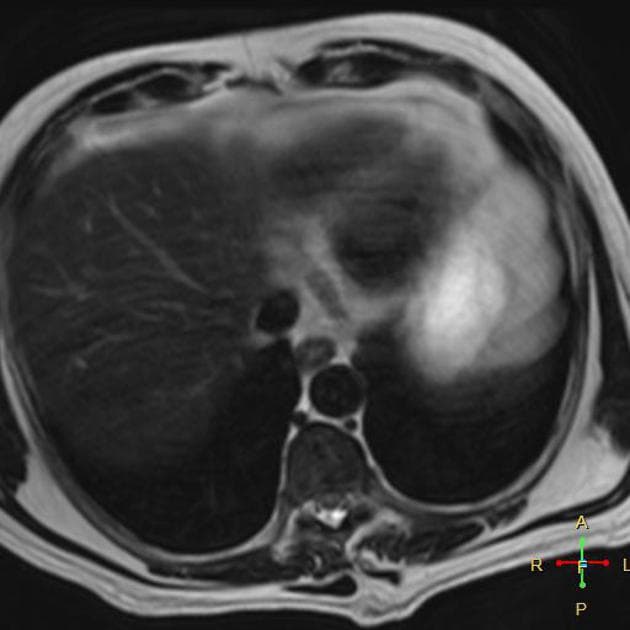

Axial C+ portal venous phase

- Tụy phì đại lan tỏa với tăng quang đồng nhất, kèm theo tổn thương mờ rìa mỡ quanh tụy và một lượng nhỏ dịch ứ đọng, phù hợp với viêm tụy cấp.

- Ở các phần được ghi hình của trung thất dưới, thấy tràn dịch màng phổi hai bên mức độ nhẹ.

- Phát hiện tổn thương dạng nang kích thước 105×75 mm ở phần phụ phải, có vách ngăn bên trong, không thấy thành phần đặc tăng quang.

Hình ảnh trên chụp CT ở bệnh nhân nữ 20 tuổi với triệu chứng đau bụng cấp tính cho thấy các đặc điểm phù hợp với viêm tụy cấp. Không thấy hoại tử.

- "Viêm tụy cấp thường biểu hiện bằng tình trạng phì đại lan tỏa và tăng quang đồng nhất trên chụp CT có cản quang."

- "Tổn thương mờ rìa mỡ quanh tụy và ứ dịch là các dấu hiệu hình ảnh quan trọng hỗ trợ chẩn đoán."

- "Không thấy hoại tử cho thấy viêm tụy thể kẽ (nhẹ), tiên lượng tốt hơn."

Viêm tụy cấp là tình trạng viêm tụy, thường do sỏi mật hoặc lạm dụng rượu. Trên chụp CT có cản quang, hình ảnh điển hình gồm phì đại lan tỏa tụy, tăng quang đồng nhất, mờ rìa mỡ quanh tụy và ứ dịch. Việc không thấy vùng tụy không tăng quang cho thấy không có hoại tử, phân loại đây là thể viêm tụy kẽ nhẹ. Các dấu hiệu đi kèm như tràn dịch màng phổi hai bên có thể do đáp ứng viêm toàn thân. Chẩn đoán phân biệt bao gồm các nguyên nhân khác gây đau bụng cấp như viêm túi mật, thủng loét dạ dày tá tràng và viêm ruột thừa. Đánh giá hình ảnh chính xác rất quan trọng để xác định mức độ nặng và định hướng điều trị.